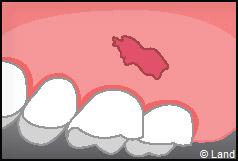

Il existe plusieurs causes qui favorisent ce processus :

– une gencive fine ou des racines proéminentes

– un brossage trop agressif

– la plaque dentaire

– des couronnes mal ajustées.

Les conséquences de cette mise à nu de la racine dentaire sont multiples, le patient peut présenter une hypersensibilité dentaire et l’aspect de ces récessions peut être inesthétique. Dans ce cas, la chirurgie muco-gingivale est recommandée et elle peut se faire de différentes façons.